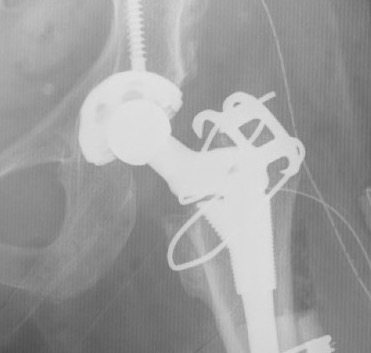

Crowe IV: Use normal acetabulum, shorten femur with subtrochanteric osteotomy + trochanteric slide

Femoral shortening / Subtrochanteric osteotomy

Technique

Vumedi subtrochanteric osteotomy for Crowe IV

Options

- transverse / oblique / chevron / step cuts

Results

Li et al BMC Musculoskeletal 2014

- systematic review of trochanteric osteotomy for DDH THA

- 37 studies and 800 hips

- no difference in outcomes (nonunion, revision) for transverse versus stepcut

Wang et al J Arthroplasty 2017

- 76 Crowe IV THA

- transverse osteotomy with uncemented stem

- 1/76 nonunion

- 1 acetabulum and 1 femoral stem revised at mean 10 years